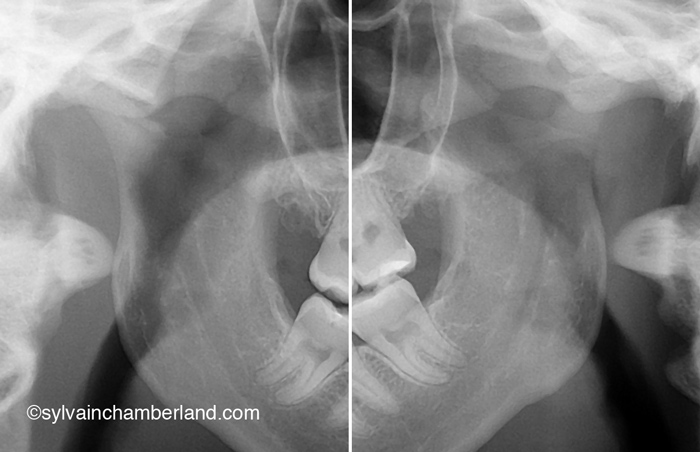

Voici les photos cliniques d’un cas semblable décrit plus haut. La béance antérieure est indiquée par les flèches noires. L’autorotation postérieure est indiquée par la flèche bleue. La résorption du condyle est indiquée par la flèche verte et la résorption de l’éminence est indiquée par la flèche bleue.

1- Il est vrai qu’une résorption condylienne bilatérale comme dans le cas présenté dans la photo de gauche cause une béance antérieure.

5- La radiographie de droite représente l’état des condyles complètement résorbés du cas clinique illustré sur la photo de gauche.

Ce patient a reçu des prothèses totales des 2 articulations temporomandibulaires.

Sur la radiographie de gauche, la plus grande barre horizontale représente la 2e vertèbre cervicale. Normalement, l’angle goniaque est situé à cette hauteur. La résorption des condyles a causé un raccourcissement de la branche montante de sorte que l’angle goniaque se trouve à hauteur de la 1re vertèbre cervicale. La petite barre horizontale indique la largeur du tractus oropharyngé. il faut avoir normalement 10 à 15 mm. Dans ce cas, il y a à peine 5 mm de largeur.